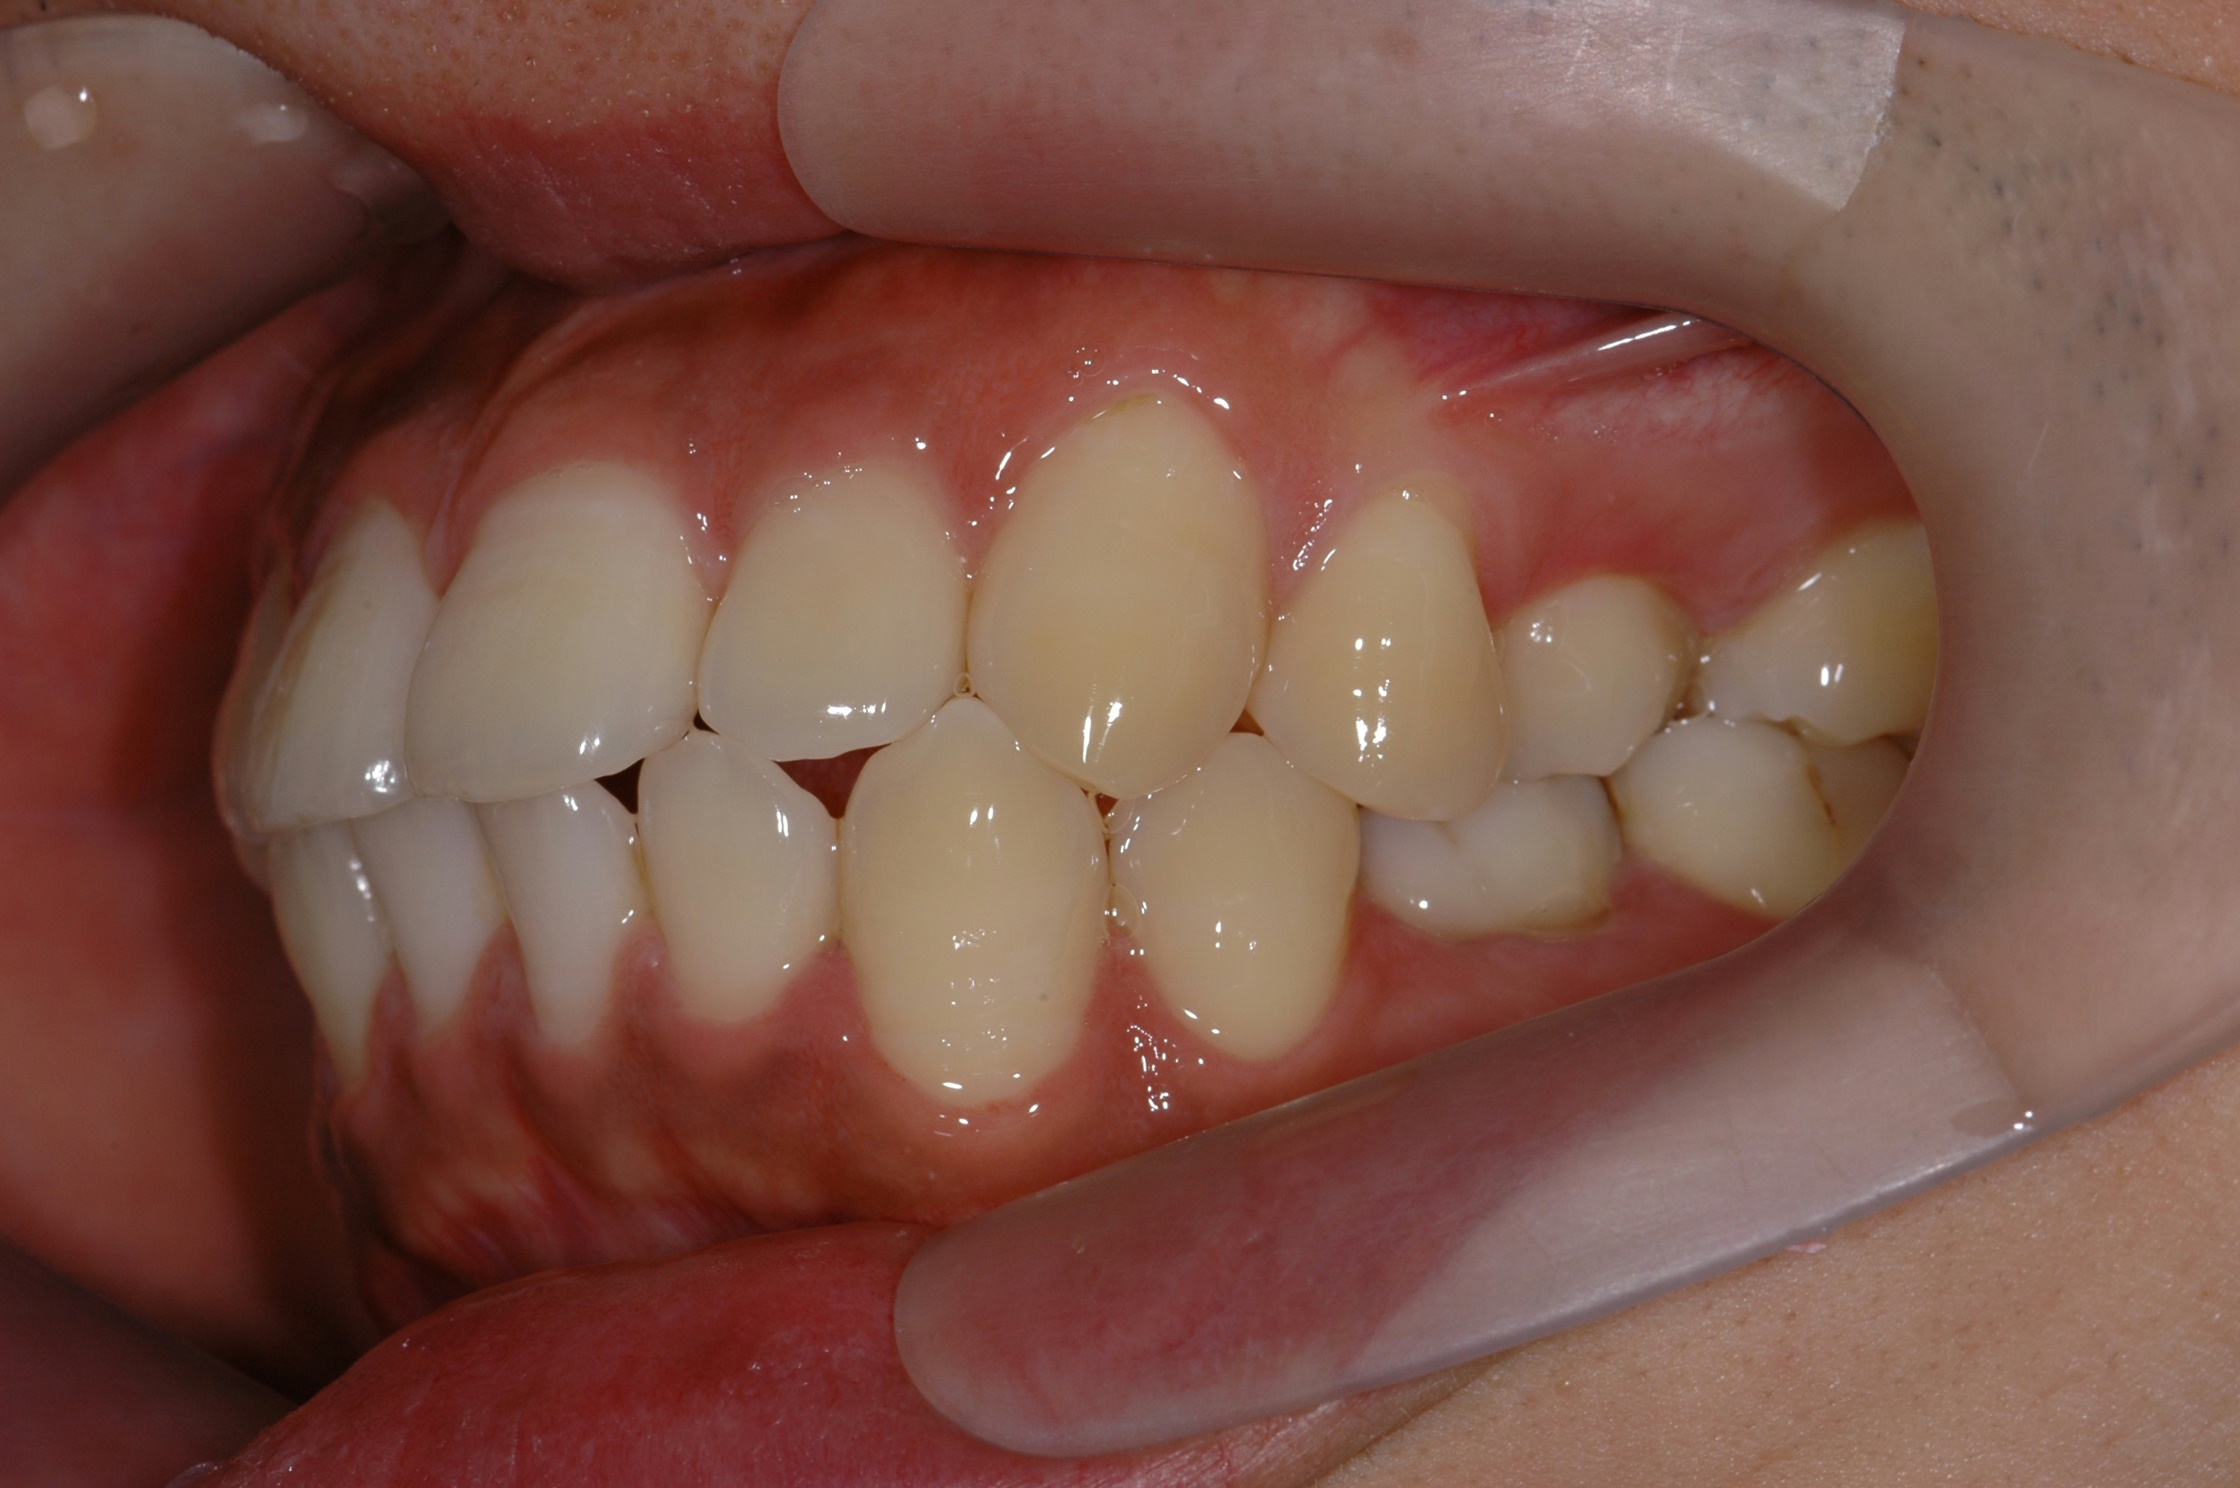

[돌출입] 돌출입